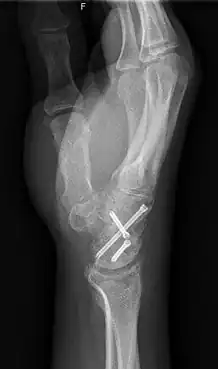

Arthrodesis is the surgical immobilization of bones within a joint to promote fusion of the joint.[5] Arthrodesis is performed most commonly on joints of the feet, hands, and spine.[6][7][8] Arthrodesis can relieve pain from arthritis and fractures.[9] This is accomplished through the use of orthobiologics such as allografts and autografts.[10] Allografts are done by creating bone grafts from a donor bone bank, whereas autografts are bone grafts from other bones in a patient's body.[10] Patient-reported outcomes following this procedure are typically positive in terms of long-term pain relief; however, the procedure also results in decreased range of motion.[11]